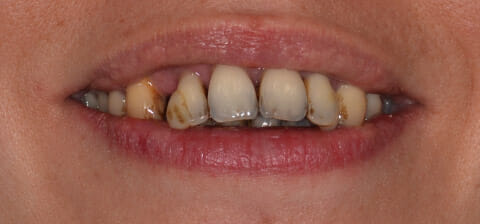

Paziente di 35 anni affetta da parodontite aggressiva generalizzata e da osteoporosi.

La paziente presentava anche un problema di spostamento evidente dei denti dell’arcata superiore, per cui necessitava di terapia ortodontica.

La paziente è stata quindi sottoposta a sedute di terapia parodontale microinvasiva eseguita con microscopio operatorio e laser.

Una volta curata la parodontite e ripristinata la funzionalità corretta della bocca sono state eseguite anche la terapia ortodontica fissa e la terapia estetica.

Il risultato è stato il salvataggio di elementi a rischio estrazione e il ripristino sia funzionale che estetico della bocca della paziente, che ha potuto ritrovare la fiducia nel suo sorriso.